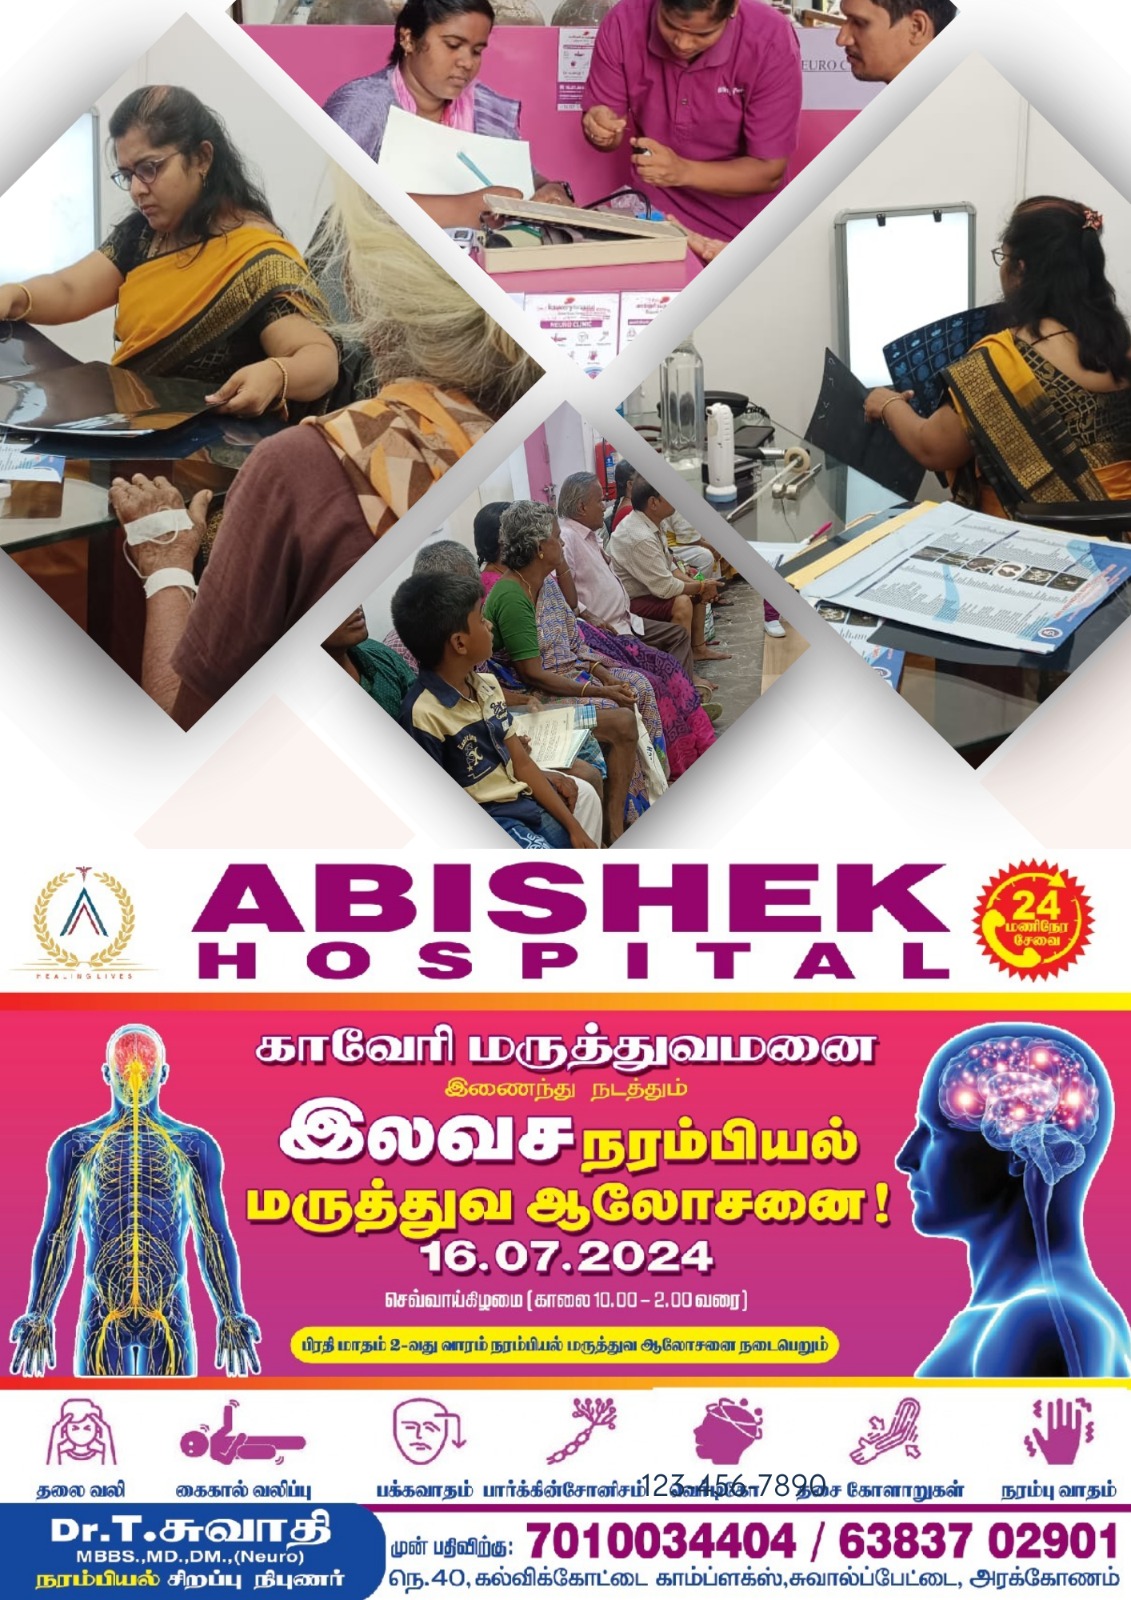

Our Treatments

Emergency

We provide 24-hour emergency care to patients who need urgent medical attention for severe injuries or illness.

Why Choose Abishek Hospital?

At Abishek Hospital, Arakkonam, we are committed to providing exceptional healthcare with a patient-first approach. Our team of experienced doctors and skilled medical professionals ensure accurate diagnosis and effective treatment using state-of-the-art medical technology. We offer a wide range of specialized services, from general medicine to advanced treatments, all under one roof. Our 24/7 emergency care guarantees immediate medical attention whenever needed.